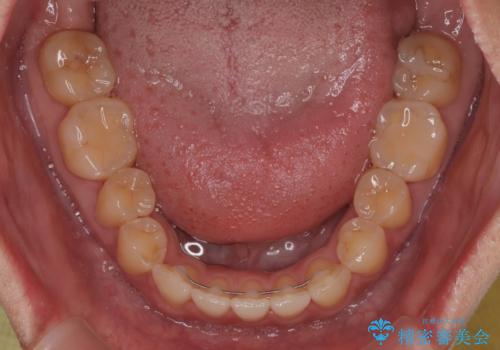

- 極端な開咬を気にして来院された患者様です。

開咬の方の特徴として、幼少期の指しゃぶりの癖や、強い舌の突出癖が挙げられます。

こちらの患者様も強い舌の突出癖が認められたため、矯正治療を行うにあたり、舌のトレーニングをしっかりと行っていただくように指示をいたしました。

開咬はインビザラインが得意とする歯列不正であるため、舌のトレーニングを行いながら、インビザラインにて矯正治療を行うこととしました。

担当医としては、もっと上下の前歯を接触させるところまで治療を進めたいという思いがありますが、今まで咀嚼できなかったものが食べられるようになったということで、この状態で治療終了となりました。